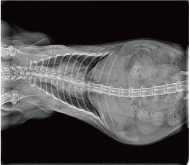

Application